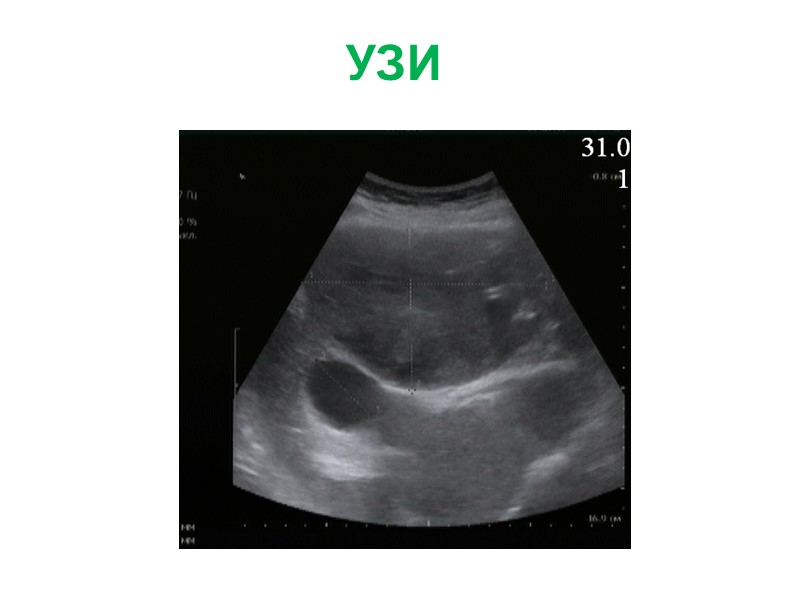

Жалобы: на боли периодические боли в эпигастрии, тошноту, изжогу Анамнез заболевания: Впервые образование левой доли печени (гемангиома) выявлено при УЗИ в 2009г. Рекомендовано динамическое наблюдение. В конце 2010г появились вышеуказанные жалобы. При обследовании отмечается увеличение образование в размерах, смещение желудка влево. Диагноз: фокальная нодулярная гиперплазия левой доли печени Больная Б., 27 л.

УЗИ УЗИ